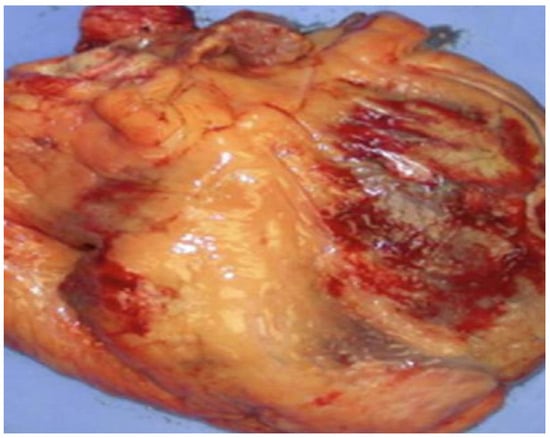

| Deshpande et al., 2016 [112] | Patients: 16 ARVC/D pediatric patients. Histopathologic observations: 6 autopsies, 6 explanted hearts, and 3 biopsies revealed massive fibro-fatty infiltration in the RV. Genetic observations: Two patients presented mutations previously reported and only one had a novel mutation of a known ARVC/D gene. |